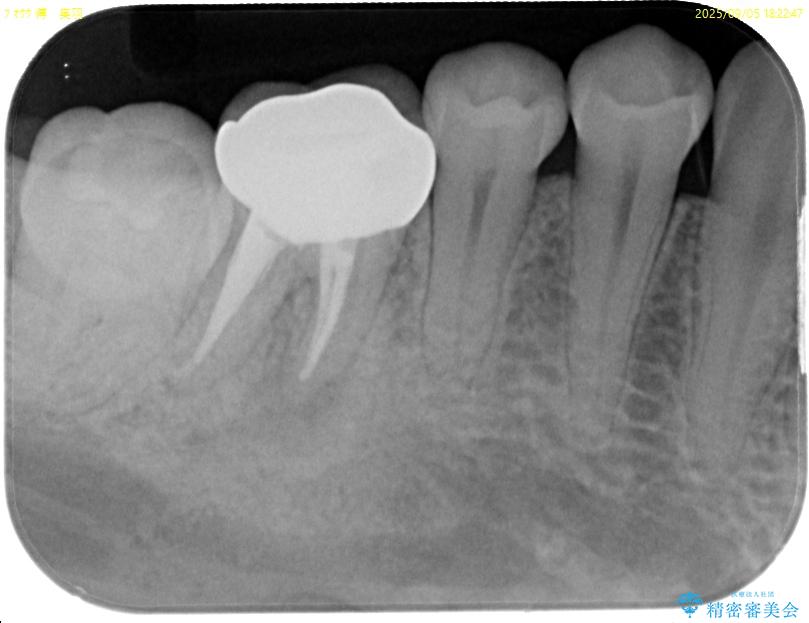

「以前に根管治療をした歯が、噛むと違和感がある」とのことでご来院された患者様の症例です。 患者様は、数年前に他院で根管治療を受けたとのことでしたが、被せもの(クラウン)は装着されていない状態でした。 噛んだときの違和感が慢性的にあり、食事中も気になるとのことで当院にご相談いただきました。 レントゲン検査では、根の先端に透過像(根尖病変の可能性)が見られ、過去の治療ではラバーダム防湿が使用されていなかったそうです。

• ラバーダム使用で再感染リスクを抑えた再根管治療+精密な補綴による長期安定を実現 治療前画像